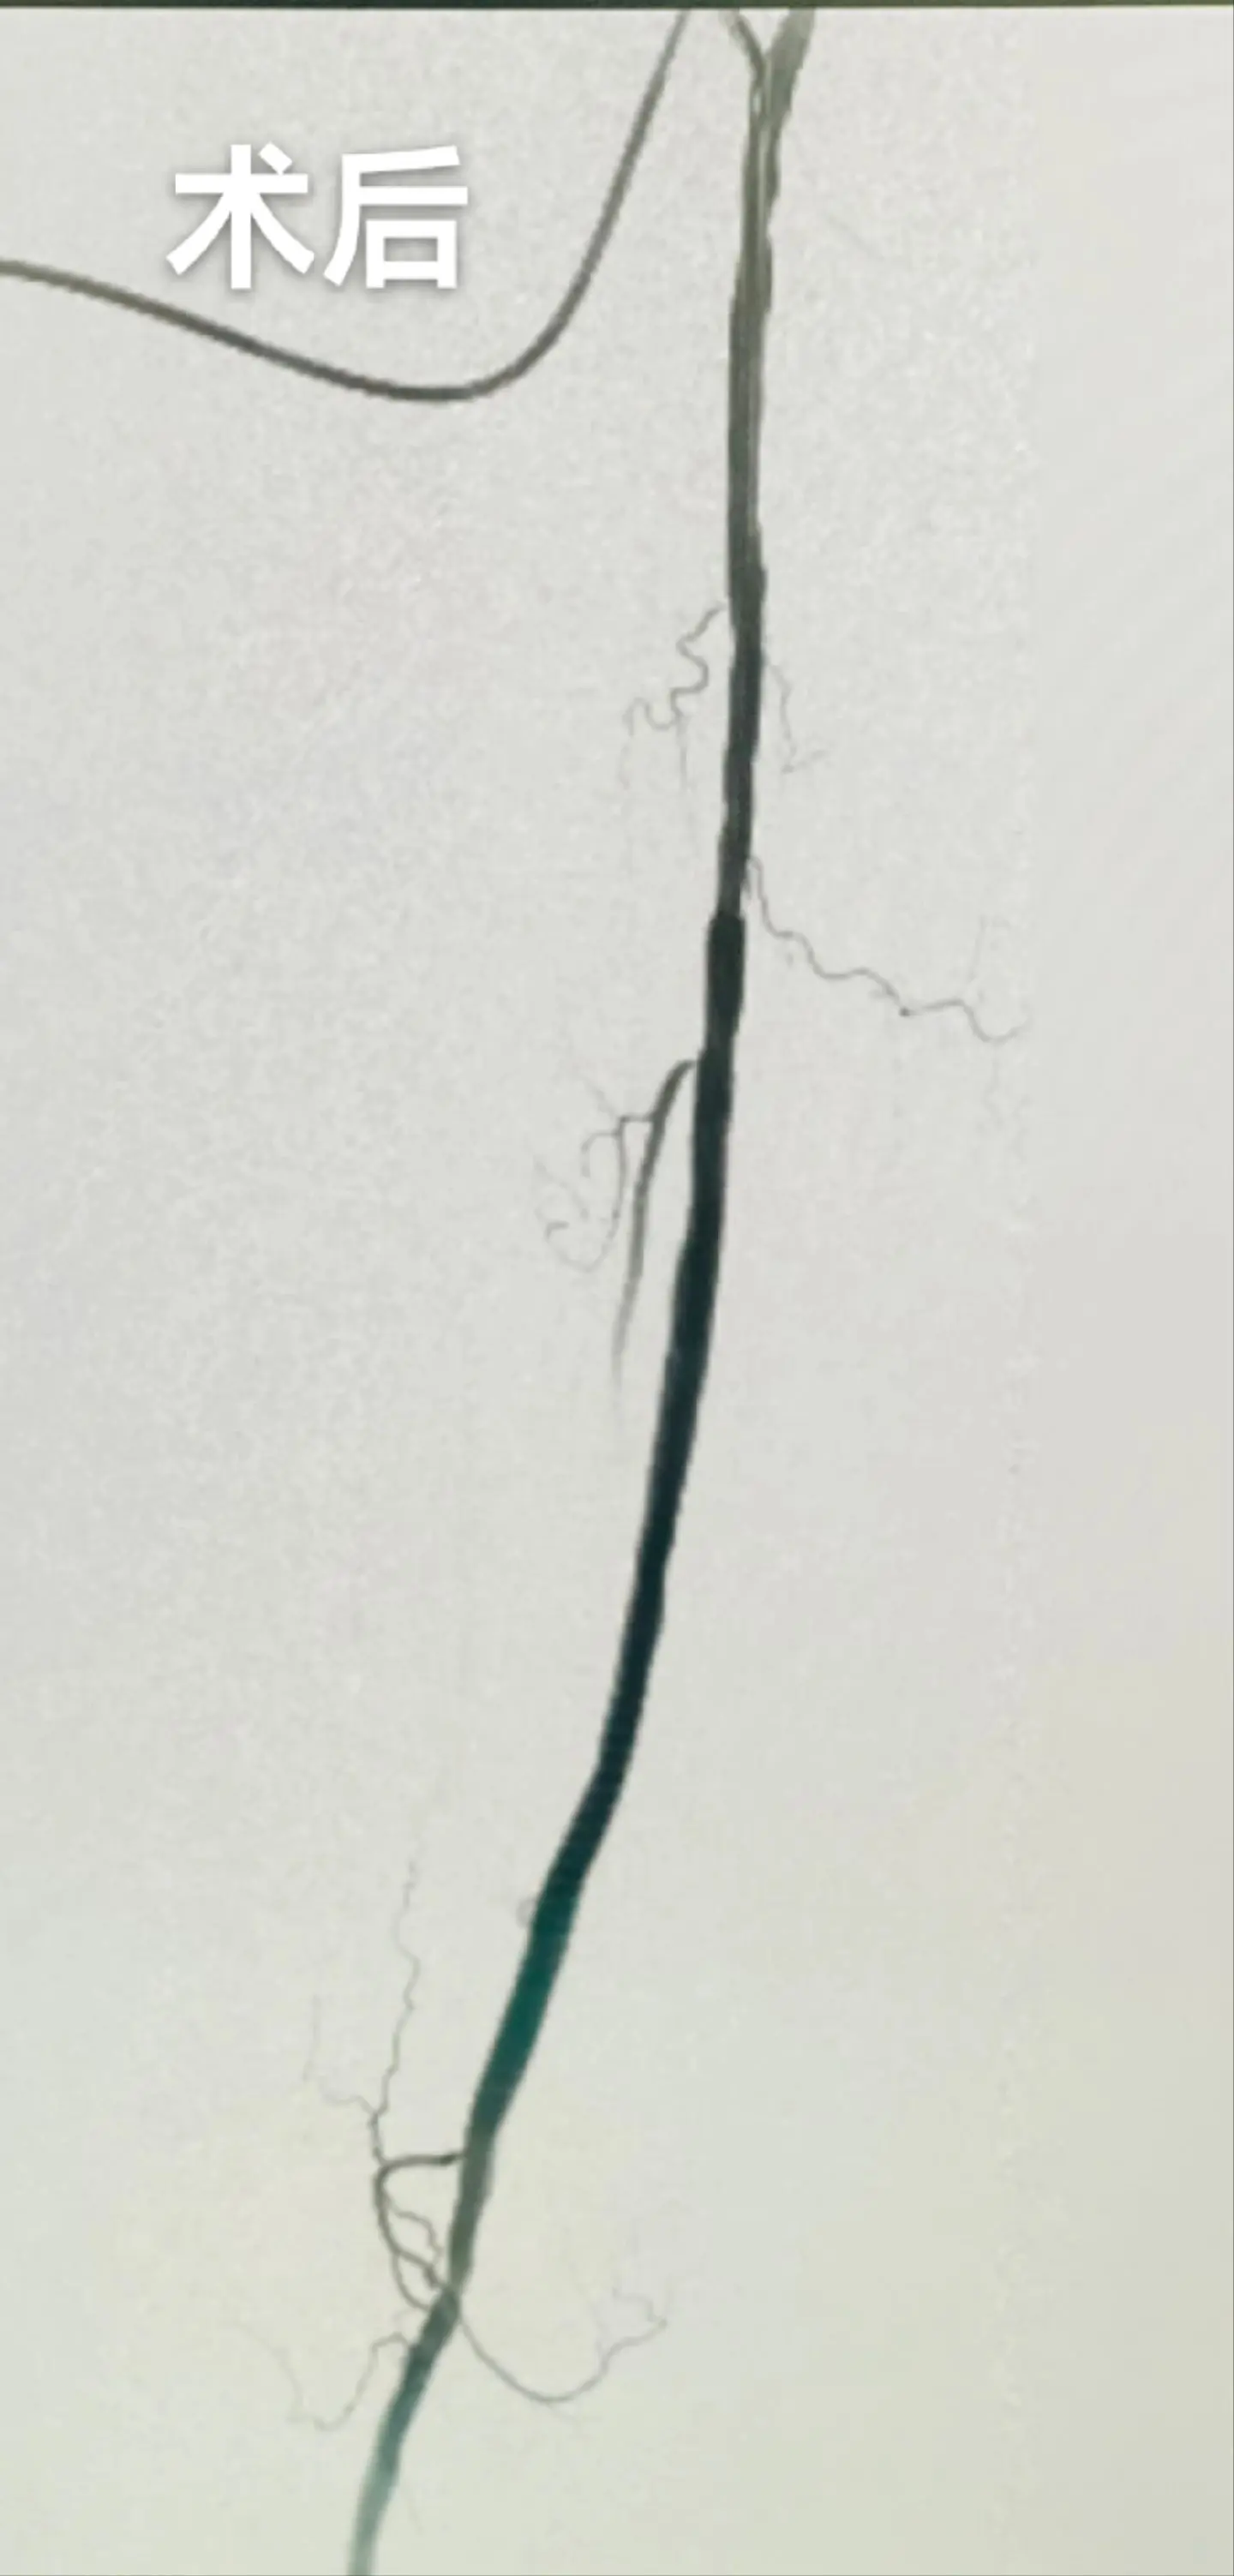

为血透患者维护生命线